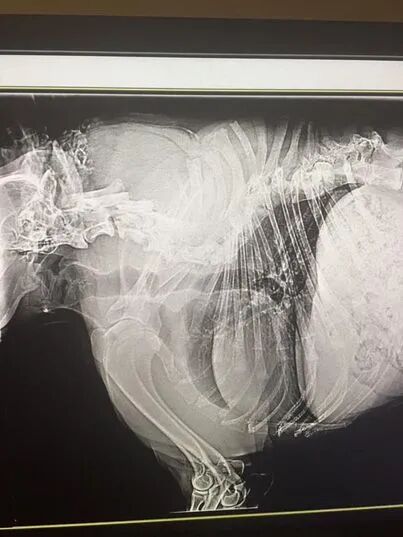

头和四肢都是正常尺寸,就是脊椎比一般的狗狗要短得多,背部不是平直的,而是倾斜的,几乎没有脖子,也就是说头下面直接就是身体,脖子部分似乎被移除了,尾巴也是畸形的,呈螺旋状。

正是因为它的外形,让它成为了一只流浪狗。当救援组织发现后,对它进行了救治,检查后发现,它缺少了几块脊椎骨,无法通过手术进行修复,只能进行简单的尾巴修复和外伤治疗。

幸运的是,卡西莫多狗并没有因为脊椎的缺少,而失去日常的活动能力,没有脖子,它就没有办法转头,只能整个身体转过来,也不能正常低头去闻嗅物体。